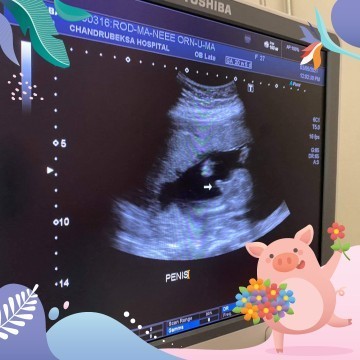

มองว่าเพศชายไหม

จากที่ดูๆ คุณหมอบอกชายล้าน% แม่ๆ ว่าชัดใช่ไหมคะ😆 แม่ไม่แน่ใจ เด็กอะไรจู๋ตั้งขนาดนั้น ยังแอบแซวหมอนั่นนิ้วน้องหรือป่าวคะ😆

โด่วมาเลย 😂